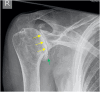

The rotator cuff is a group of four muscles and tendons surrounding the shoulder joint providing it strength and stability. The rotator cuff consists of the subscapularis, supraspinatus, infraspinatus and teres minor. Many shoulder complaints are caused by rotator cuff pathology such as impingement syndrome, tendon tears and other diseases e.g. calcific tendonitis. Diagnosis starts with clinical history and physical examination, after which imaging is often used to help confirm clinical findings depending on the differential diagnosis. The aim of the article is to review the frequently used imaging modalities to assess the rotator cuff and cuff-related disease, specifically focusing on radiography, ultrasonography and magnetic resonance imaging. This article will outline the advantages and disadvantages for each modality and illustrate typical radiological findings of common rotator cuff pathologies.